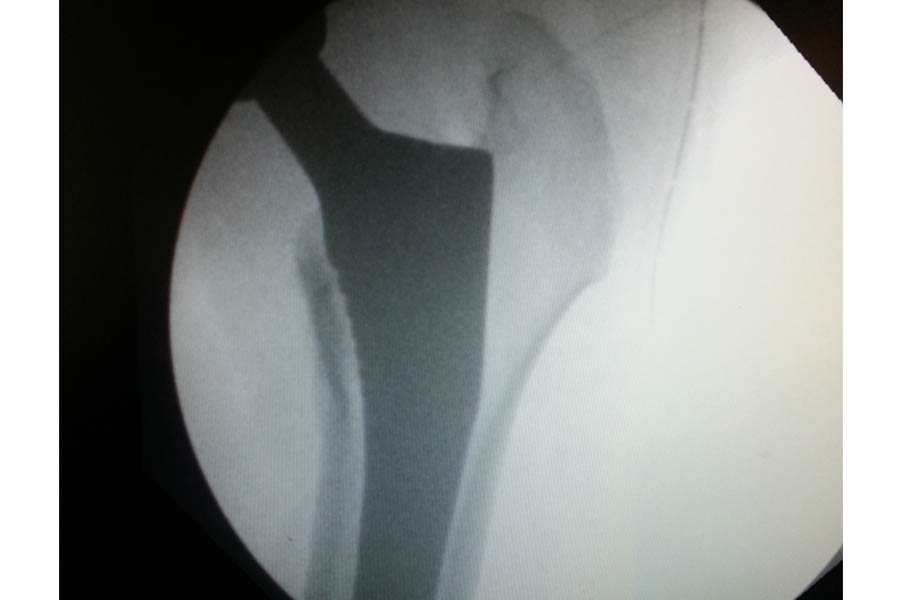

Difficult Replacement

Case 1

Trauma